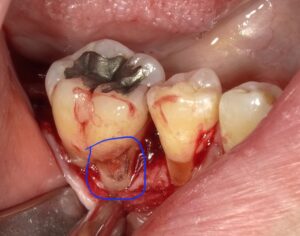

コーヌスデンチャーとは残っている歯に冠のような金属を被せてその上にさらに金属を被せる

2重の冠でできた入れ歯になります。茶筒の原理で固定されるため安定感が高く、審美性や装着感に

優れています。ドイツで開発されたテレスコープデンチャーの一種です。

画像の様なイメージになります。針金を使いませんので

見た目がよくまた維持力も大きくとても良好な義歯となります。